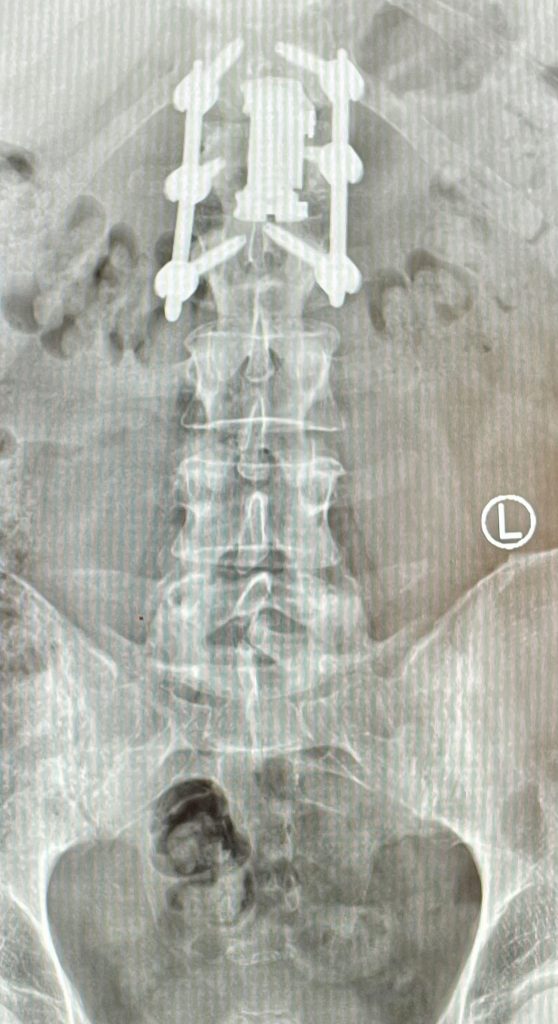

La cementación vertebral es un tratamiento contra el dolor, que consiste en introducir de manera percutánea cemento dentro de una vértebra fracturada, a través de una cánula. Previamente se intenta la corrección de la deformidad vertebral mediante el uso de unos balones hinchables.

Es un procedimiento mínimamente invasivo, se realiza en quirófano de forma ambulatoria, generalmente bajo sedación y anestesia local. Se emplean incisiones de menos de 5mm sobre la vértebra . Utilizando un balón que se introduce a través de una cánula, para crear una cavidad dentro de la cual se inyecta el cemento.